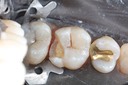

Joe Cha #29 die